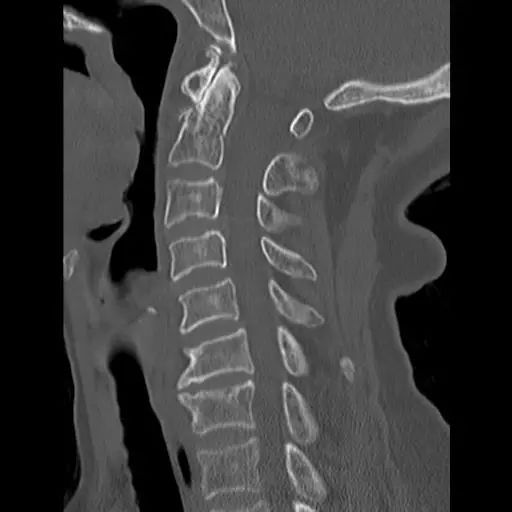

患者,男性,75岁,因外伤致颈部疼痛伴活动受限7天入院。患者入院前在当地医院确诊为:枢椎齿状突骨折Anderson-D’Alonzo分型Ⅱ型。

对于本患者来说,齿状突骨折后导致寰枢椎不稳,极易引起延髓或椎动脉损伤,严重者当场死亡。但患者同时合并严重胸腰椎后凸畸形,颈部后伸受限,不具备前路手术条件,这就给其治疗更增加了额外的困难。而由于手术部位延髓及椎动脉等血管神经密布,手术难度高、风险极大,稍有不慎,患者就会有生命危险。而患者家属在了解到手术的危险性后,曾自行到上级医院咨询专家,上级医院专家考虑围手术期死亡的风险,对于本例患者亦不愿提供手术治疗的机会。

患者经充分咨询了解,选择了枣庄市立医院脊柱外科主任王存平为其治疗。面对患者和家属期盼的目光,王存平明白这是患者最后的希望,故而没有胆怯和退缩,大胆提出了齿状突骨折后路切开复位C1、2椎弓根钉棒系统固定的手术方案。由于患者年龄较大,存在脊柱严重后凸畸形,俯卧位极度困难,全麻插管难度大,麻醉风险极大。麻醉科李传东和宓云飞医师克服重重困难,成功完成麻醉。在他们得力的麻醉和监护下,王存平仔细分离、细心操作,每一步都确保动作稳稳完成,最终成功实施了手术。

经过全程监护和系统治疗,患者术后恢复良好,骨折解剖复位,复查X线及CT显示固定位置佳,术后3天下地行走,术后4天即出院回家休养。